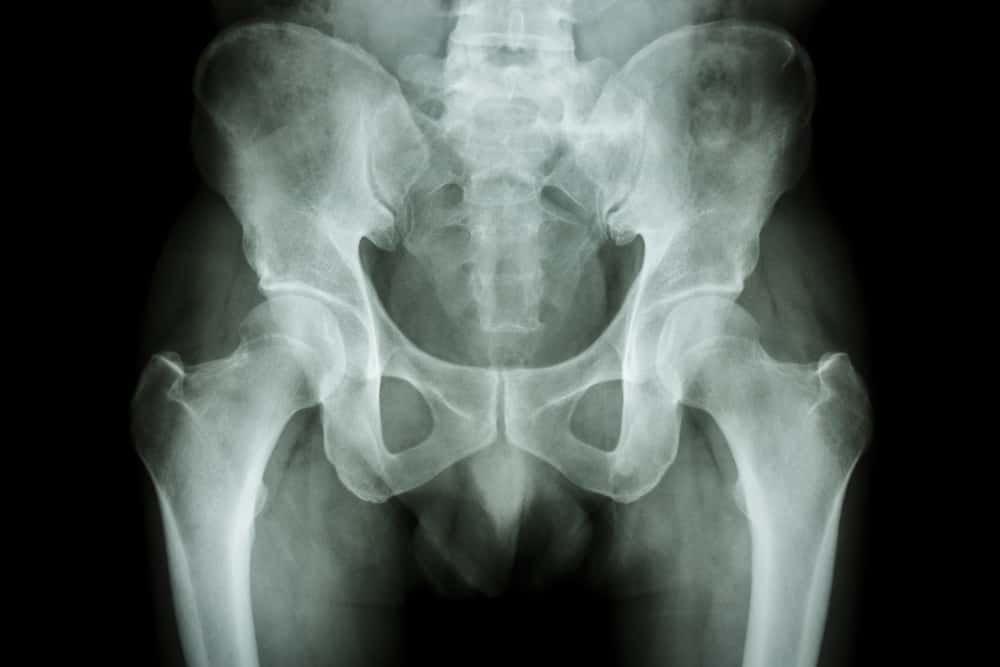

Pregnancy-related Pelvic Girdle Dysfunction

Pregnancy-related pelvic girdle pain is a collection of symptoms caused by natural changes to the muscles and ligaments during pregnancy (meaning that they might have to work slightly differently to how they did before your pregnancy), plus the additional changes in posture to accommodate your growing baby.

Symptoms of PRPGD may include pain over the pubic bone at the front in the centre of your pelvis, pain across one or both sides of your lower back or pain in the area between your vagina and anus (perineum). In some cases, the discomfort can travel down your legs.